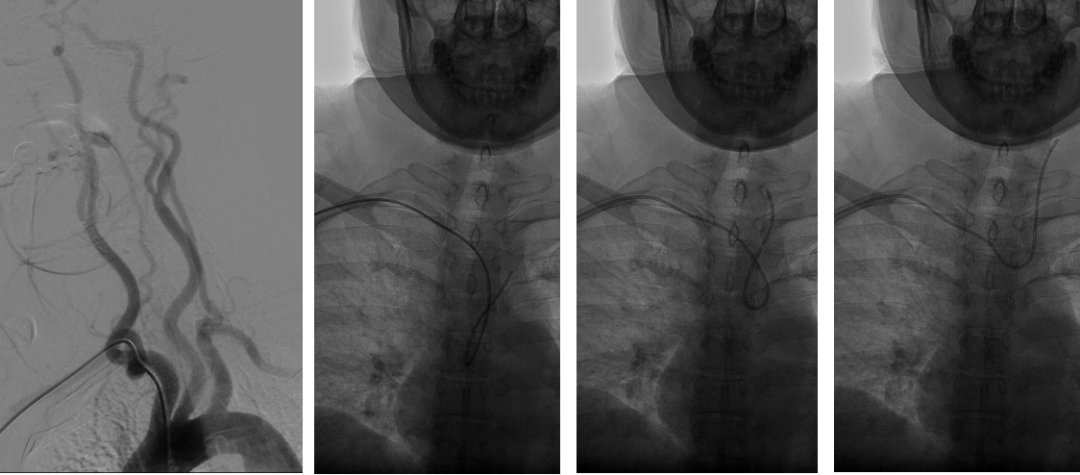

入弓:

泥鳅导丝辅助下,将Pigtail猪尾巴管送入升主动脉,行主动脉弓造影;完成造影后,放入泥鳅导丝把猪尾巴管撑直,然后将泥鳅导丝和猪尾巴管一同退出体外;也可以沿猪尾巴管放入0.35in 260cm交换导丝,保留导丝交换出猪尾巴管,再由SIM2管沿交换导丝放入主动脉弓;或此步骤用泥鳅导丝将SIM2管带入主动脉弓。

SIM2导管过弓要点

右侧为升主动脉,左侧为降主动脉;升主动脉部成袢易损伤主动脉瓣,可能致心律失常,慎用;通常 在降主动脉成袢;导丝进入降主动脉后,再部分推入SIM2导管,撤导丝,轻轻退并 顺时针旋转导管,成袢;对于3型弓,导丝过弓可能困难,建议导丝塑大弯,路图下过弓。